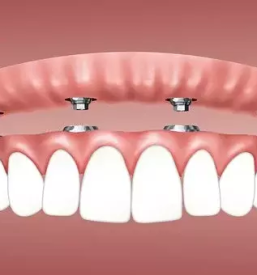

Pri nas smo specializirani za različne storitve na področju zobozdravstva. V naši zobozdravstveni ambulanti